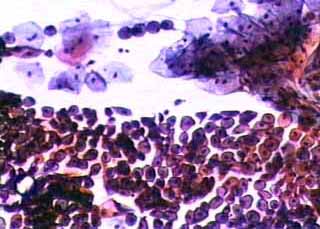

Αλεξ. Αλεξ. 57 ετών, στο ιστορικό 3 καισαρικές τομές, από 7ετίας στην εμμηνόπαυση. Ξηρότης κόλπου, δυσπαρεύνοια. Κατά τα αλλα, ασυμπτωματική.

Κολποσκοπικώς καλη επιθηλίωση τραχηλου, είκονα ατροφίας επιθηλιου, δοκιμασία lugol αρνητικη. Δοκιμασία οξικού οξέως δεν έγινε, επειδή σε γυναίκες με ατροφία επιθηλίου δημιουργεί άμεσα δυσάρεστη συμπτωματολογία. (εντονο αίσθημα καύσους, ενίοτε και πόνος στο υπογάστριο)

Papanicolaou: Τυπική εικόνα ατροφίας επιθηλιου, με παρουσία πληθωρας βασεοφίλων κυττάρων της παραβασικής και λιγώτερο της διαμέσου στιβάδος, με φυσιολογική δομή και την αναμενόμενη πολυμορφία της ατροφίας του επίθηλίου. Εντυπωσιάζουν οι σχετικά μικροί πυκνωτικοί πηρήνες με αλλαγή της σχεσης κυτταροπλασματος - πυρήνα, που σηματοδοτουν, ότι δεν προκειτια για κύτταρα με εξελικτική ικανότητα. Στο υπόστρωμα επισης κυτταρα της επιφανειακής στιβάδος.

Αρνητικό για κακοήθεια.